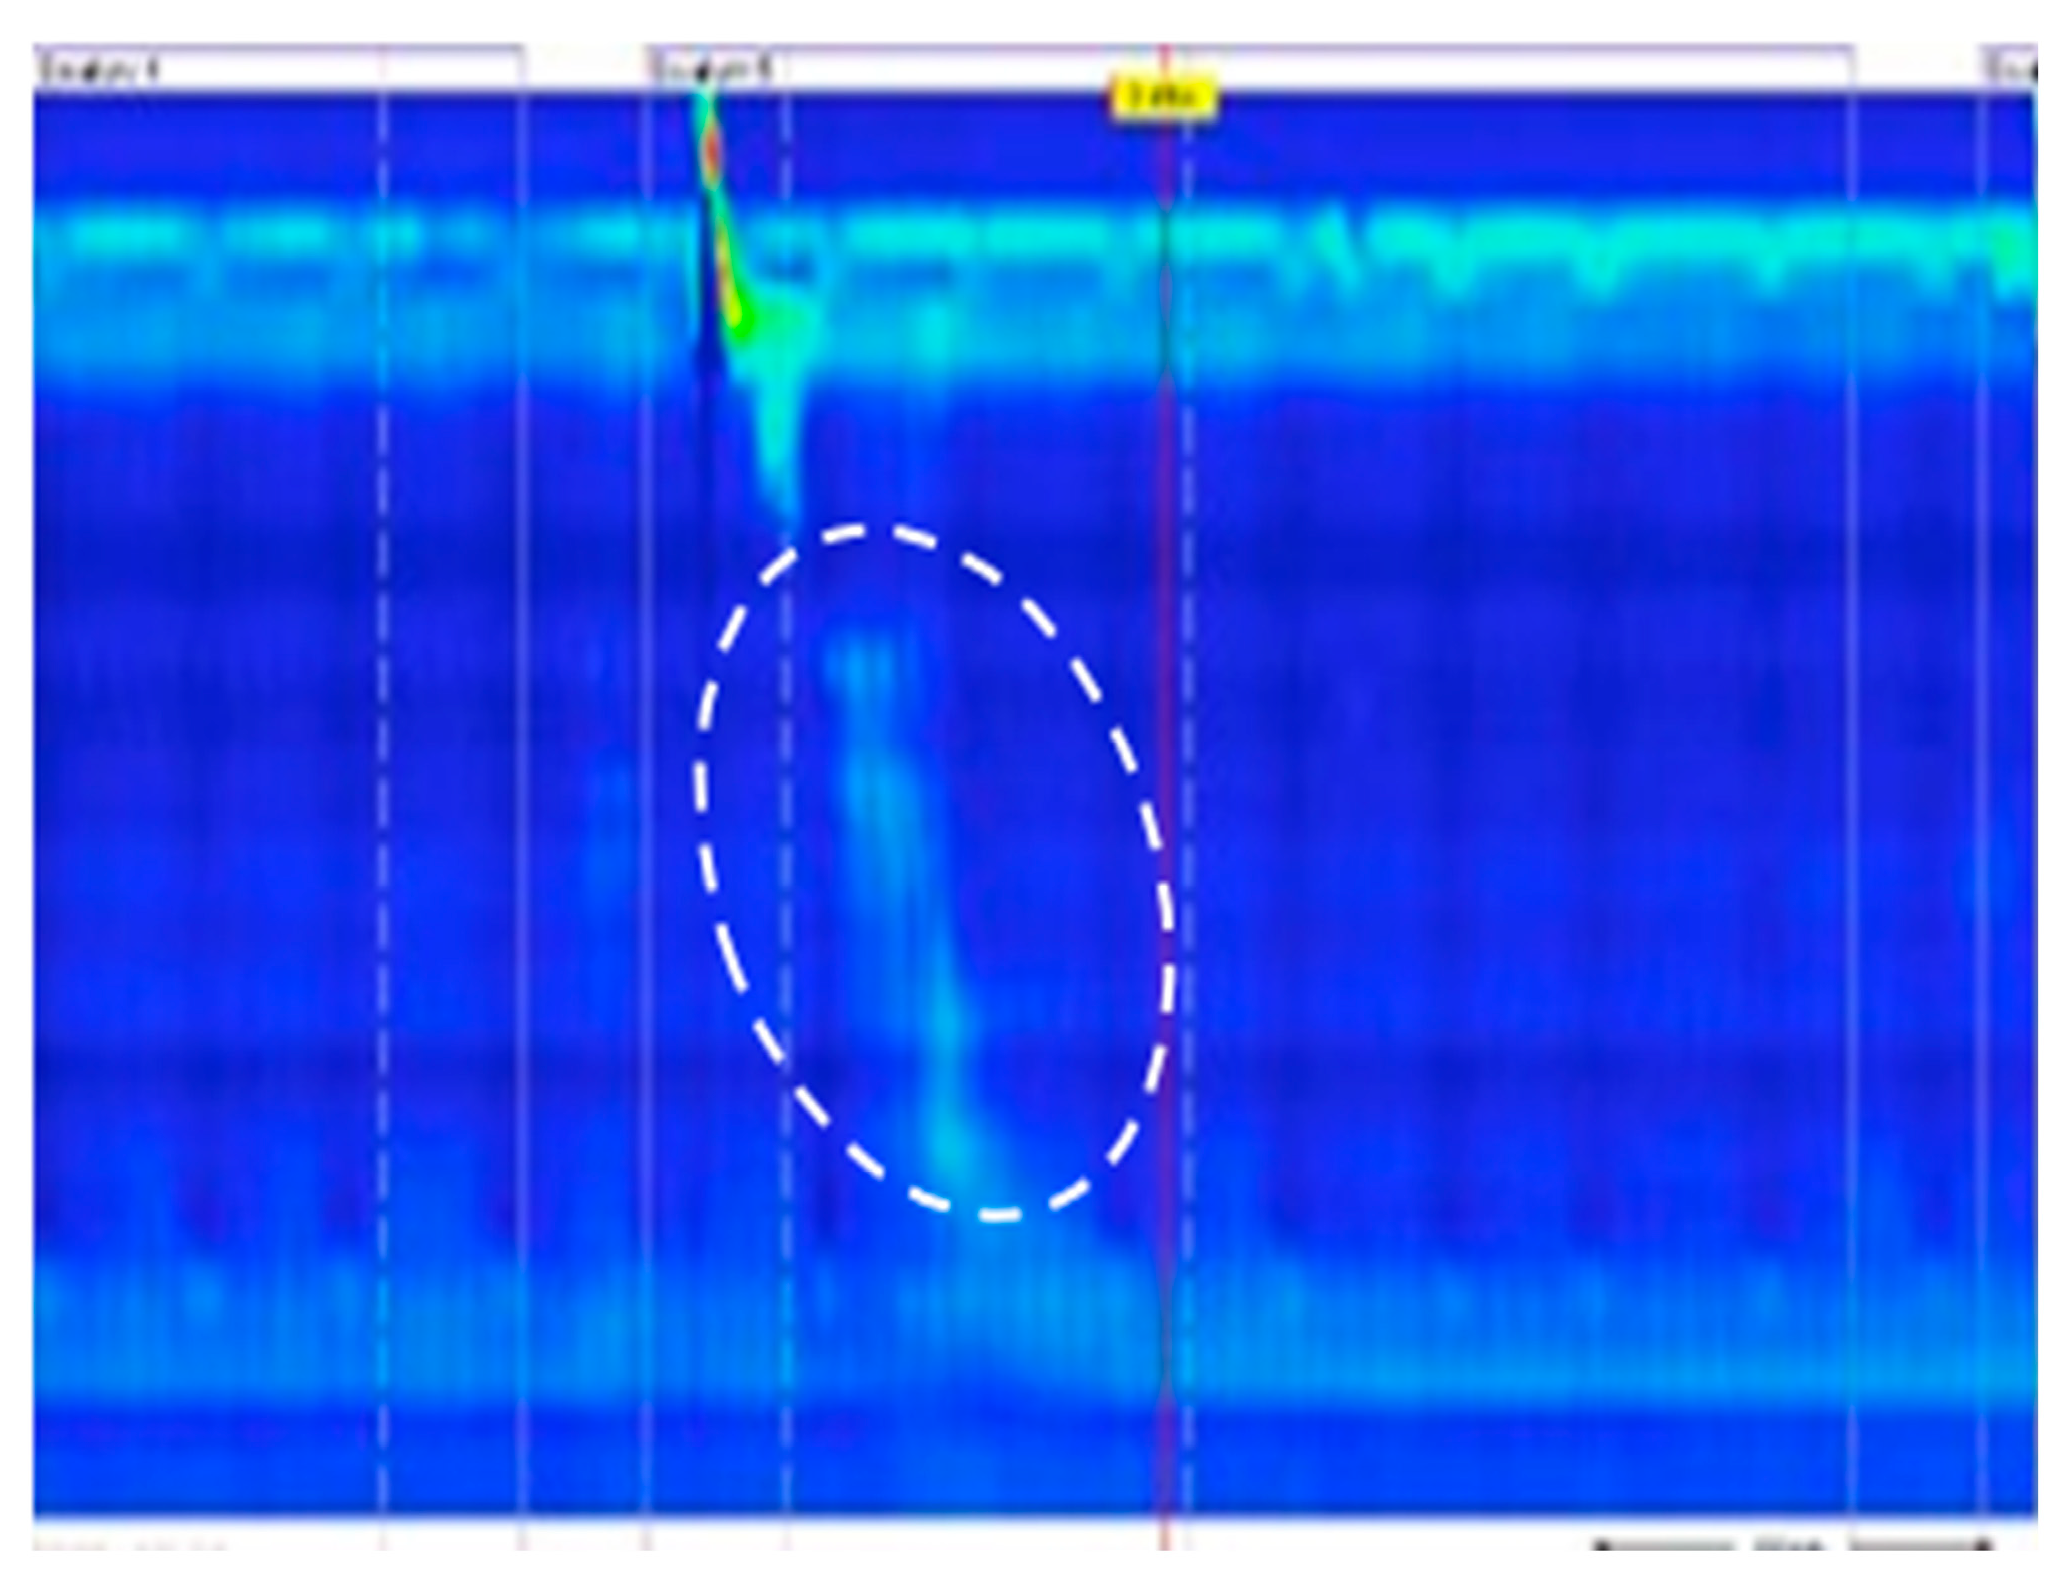

8. Advancement in HREM-Based Provocative Testing: The Supine Position Straight Leg Raise (SLR) Test